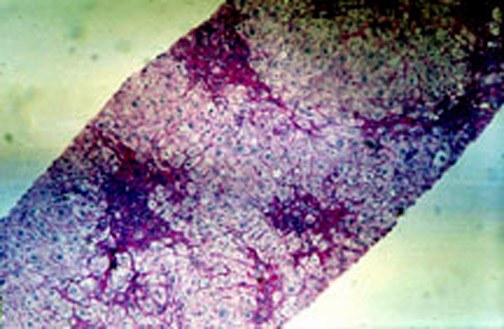

8-4-4.jpg (72265 bytes)

Fig. 8-4-4 Amiodarone hepatitis

54 year old male taking amiodarone for many years developed clinical hepatitis: ALT 780, AST 339. This slide demonstrates hydropic swelling of hepatocytes, focal cell necrosis with inflammatory reaction and cytoplasmic cholestasis. TheReview of Pathology of the Liver:Table of Contents foamy appearance is due to phospholipidosis present practically in every case  and is due to accumulation of

sphingomyelin in hepatocytes. (see Em Picture below).